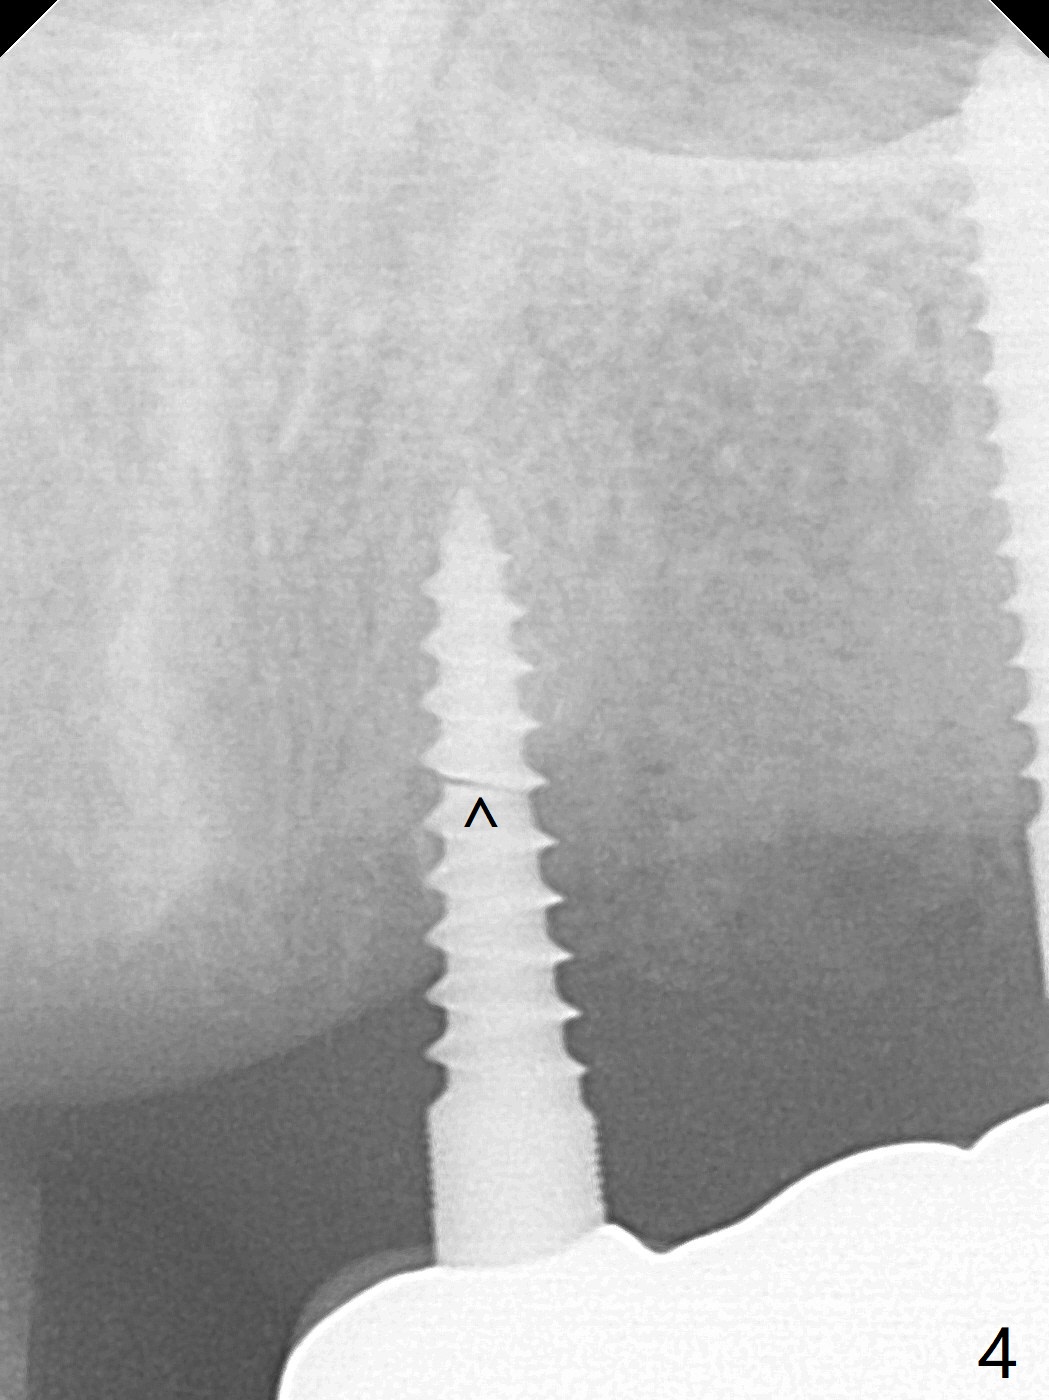

A 65-year-old woman will return to clinic with chief complaint of "loose top left implant bridge" 2.5 years post cementation. It appears that the implant at #9 is placed into the incisive canal (Fig.1 *) with coronal implant thread exposure (>). If it is true that the problem is #9. The denture tooth #8 will be removed so that the upper partial denture will be used a guide. One-piece implants will be placed at #8 and 10. The implant at #9 will be removed for bone graft as a future implant site, since the implant at #10 is 2 mm in diameter, vulnerable to fracture under mastication. If her vein is thin for PRF, consider using GEM21S to hydrate cortical bone. In fact the implant at #9 fractures at the junction of bone loss (Fig.4,5 ^). Full-mouth CT will be taken. Alginate impression will be taken for #8-10 surgical stent and provisional. Remove #8 denture tooth for implant placement with incision. Section the FPD between #10 and 11 for #10 implant placement using #9 broken implant as a guide when PA is taken. Remove the fractured implant and make a provisional.